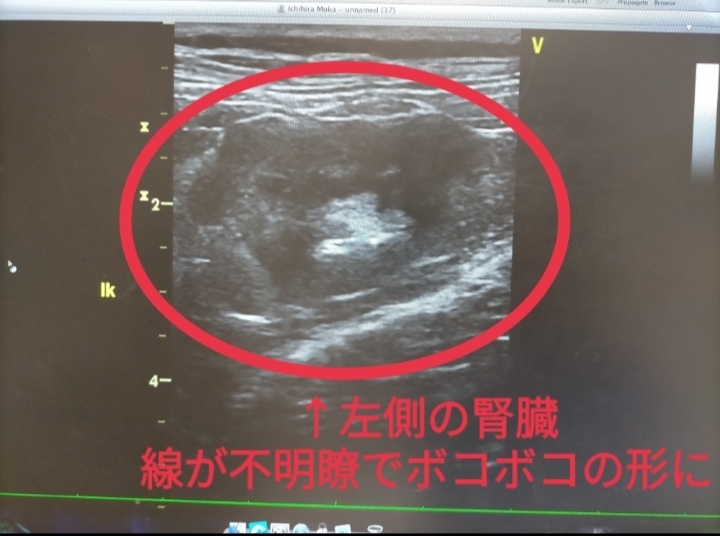

2024年11月5日🏥

いつものように検査をしていたら、

左側の腎臓だけ形がボコボコに…💦

今はステロイド治療ですっかり綺麗な形に戻り、その後薬を減らしてもずっと維持できているので、一過性の炎症の可能性もあるのですが…

実は発見当初、リンパ腫再発(転移疑い)の可能性が非常に高く、気が気ではありませんでした😭